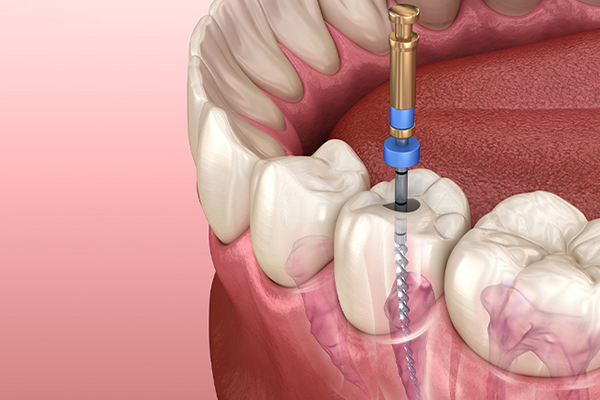

With over 27 years of clinical excellence in Thane, Dr Tamhane's DenTrio Dental Implants & Laser Clinic has been transforming smiles and changing lives. Our multi-specialty team combines decades of expertise with cutting-edge dental technology to deliver exceptional, patient-first care.